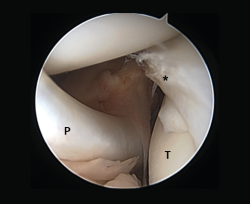

Other tests that contribute to the diagnosis are stress valgus radiographs (local anesthesia infiltration is advised in order not to underestimate the test), magnetic resonance imaging (MRI) and arthroscopic exploration (Figure 1).

Figure 1. Arthroscopic view through the anterolateral port of a positive drive-through sign with abnormal aperture of the internal compartment secondary to insufficiency of the medial collateral ligament. Right knee.